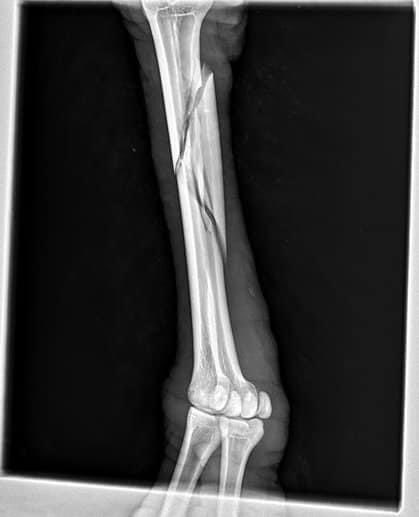

وبالتالي إذا انكسر الجزء السفلي من ساق الحصان ،فإن العظام الموجودة فيه لا تنكسر فقط؛ بل غالبا ما تتهشم تماما.

هذا يجعل من المستحيل إصلاحها أو إعادتها إلى شكلها الأصلي في بعض الحالات حتى لو تم تجميعهم بطريقة ما ، فإن الحصان سينتهي حتماً بعظم ثابت بشكل سيء.

لأنه من الصعب جدًا التئام ساق الحصان المكسورة بشكل صحيح بالإضافة إلى أن تدفق الدم للحصان يعتمد على حوافره

كما أنه من الصعب أن يبقى الحصان ساكنًا لفترة طويلة تسمح لعظامه بأن تُجبر وإن تم جبر ساقه فإن تكلفة العلاج باهظة